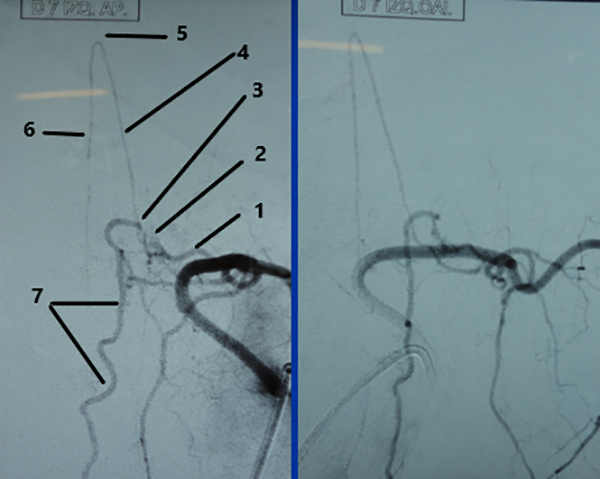

Figura 10: Caso #2. ADM preoperatoria en AP y OAI. La misma arteria radiculomedular D 7 izq. (1) da origen a la arteria de Adamkiewicz (4) y a la FDAVE (2); pie de vena de drenaje (3); horquilla de la arteria de Adamkiewicz (5); arteria espinal anterior (6) y vena espinal posterior (7).